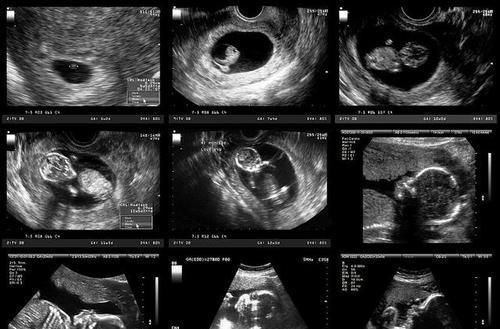

文章插图

哪些因素有可能造成畸形儿问题?根据现有的结论,并结合现实状况,目前可以给出下列几点可信度较高危险源,希望各位准妈妈注意一下。